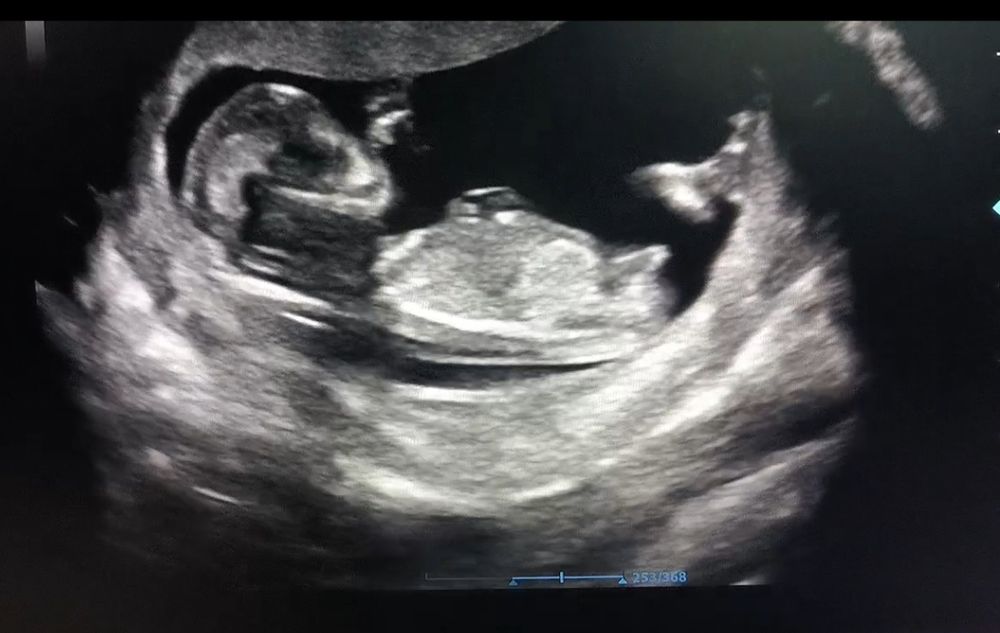

Половой бугорок🌸

Уклон небольшой как девочка, но вот длина смущает 😅, больше в сторону мальчика)

Погранично как-то у вас... Нельзя точно сказать

Больше на мальчика пока похоже 🐣

А я бы на девочку подумала))

У меня так девочка выглядела в 12 недель🤗

Мальчик

Вам еще не сказали пол? У нас очень похоже наклон и длина 😂 так интересно

Найс, ждём 2 скрининг♥️ Я пересматривала видео с УЗИ раз 100 и каждый раз наклон менялся, но не было такого чтобы прям вверх смотрел😅

Юлиана, я сегодня пошла) на 16неделе сказали девочка)

Найс, сегодня сказали, что будет мальчик))